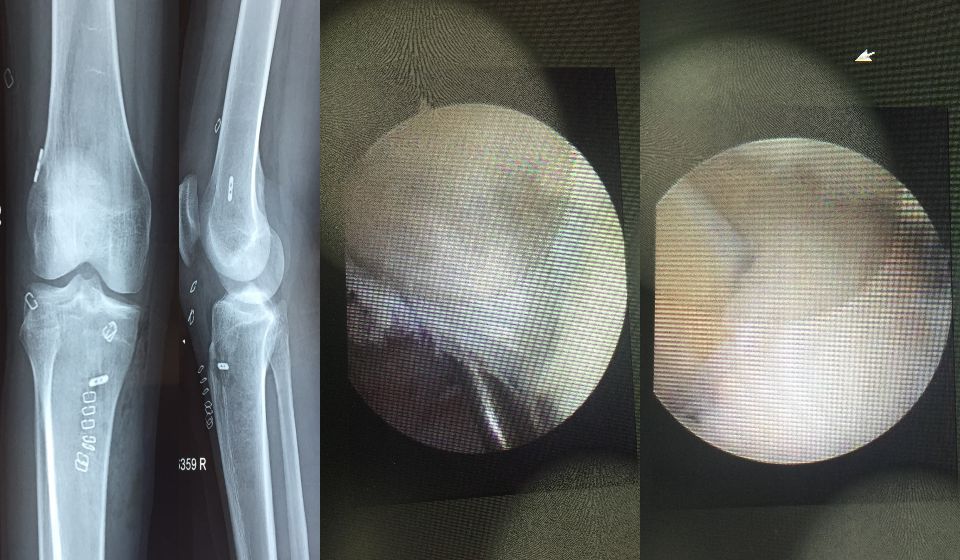

A diagnosis of ACL injury is based on a thorough physical examination of the knee. The exam may include several tests to see if the knee stays in the proper position when pressure is applied from different directions. An X-ray and MRI (magnetic resonance imaging) or, in some cases, arthroscopic inspection will confirm a diagnosis of a torn ACL.